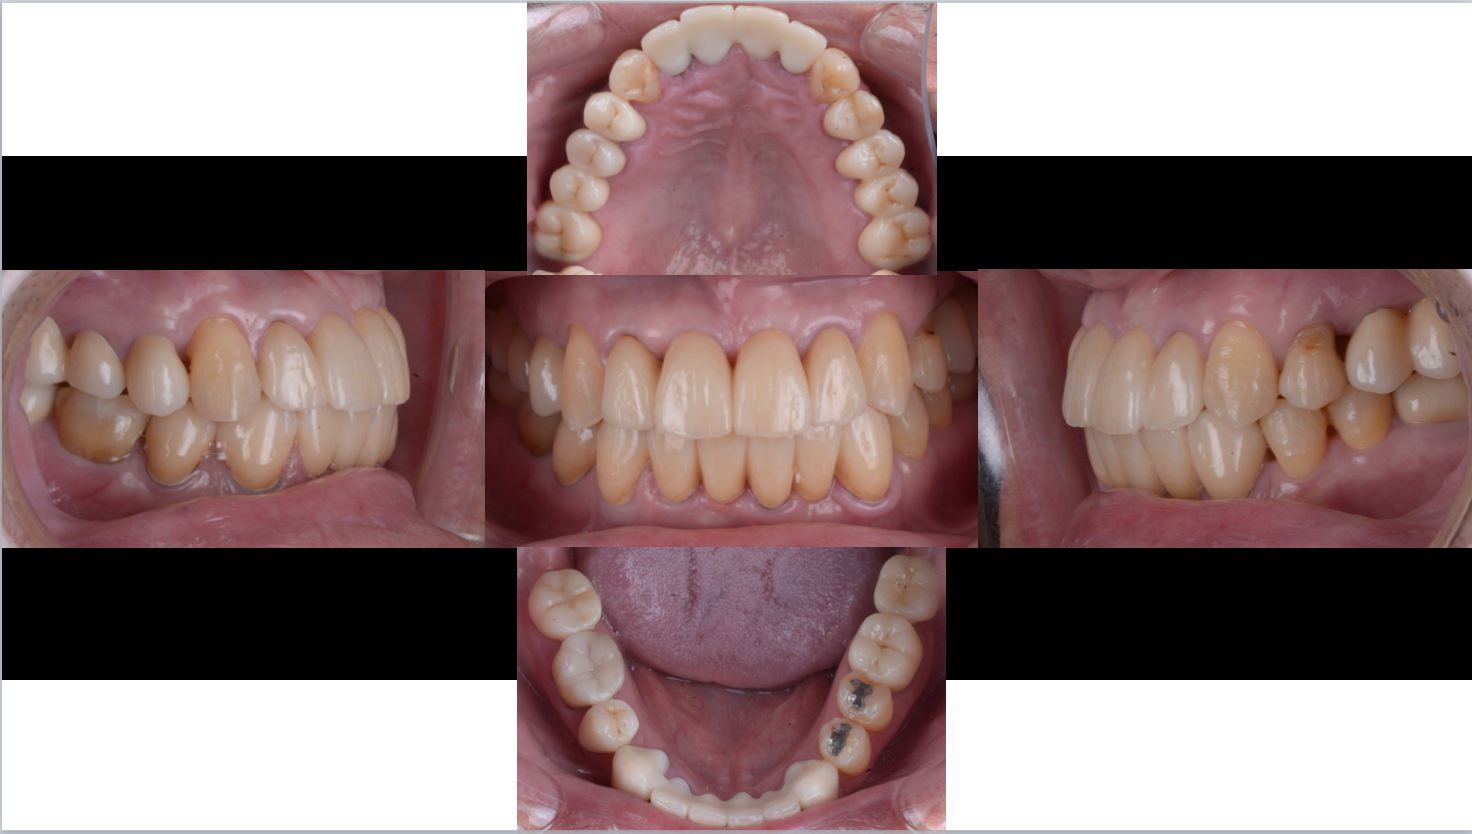

↑個々の歯の生えている向きに合わせて仮歯を装着しました。治療前は無理やり歯並びの悪い状態に被せ物が入っていましたが、どうですか?こうしてみるとかなり前歯を中心に個々の歯の向きが様々なのが理解できると思います。

これが今現在の歯の生えている向きで、これを矯正治療で正しい位置と向きに改善します。

セラミックによる噛み合わせが獲得されました!正常機能ももちろん有しています!!

この方実はやや受け口だったのですが無理のない範疇で正常な噛み合わせを前歯に与えることができましたね。

当初左にずれていた顎がかみ合わせに治療によってほぼ真っ直ぐになりました。

前歯の噛み合わせも改善できました!安定した再現性のある噛み合わせのポジションを患者さんもご理解し、何事もなく術後5年が経過しました。